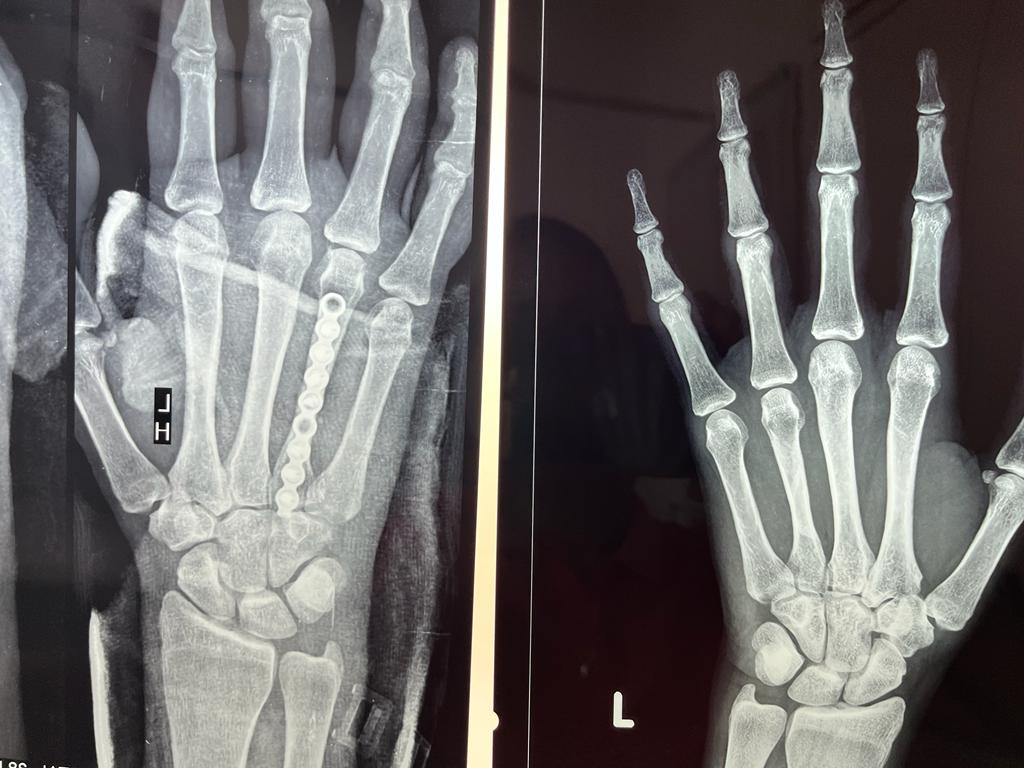

Pre and post of pics of 3 months old fracture 4 th metacarpal with pain shortening of finger and loss of knuckle prominence